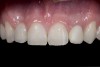

(20.) Facial view of final single-wing, modified zirconia resin-bonded bridges.

Figure 20

(21.) Smile view.

Figure 21

(22.) Right lateral view.

Figure 22

(23.) Left lateral view.

Figure 23

(24.) Occlusal view.

Figure 24

When the patient returned, the fit was evaluated in the mouth. Once verified, the internal surface of the framework was etched with a 9.5% hydrofluoric acid for 90 seconds and then salinized. After etching the enamel surface with phosphoric acid for 30 seconds and applying the primer (Single Bond Plus, 3M ESPE) to both the internal surface of the framework and the enamel, the zirconia bridge was bonded with a dual-cure resin cement (RelyX™ ARC, 3M ESPE). After the procedure, the patient ended up with a long-term, high-strength esthetic restoration advantaged by the bonding potential of fledspathic ceramic (Figure 20 through Figure 24). Six years after placement, the prosthesis had remained in place with no complications.